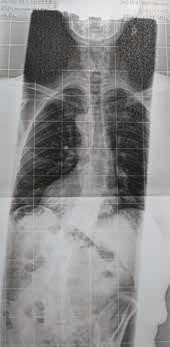

Die Behandlung von adoleszenten idiopathischen Skoliosen (AIS) im Bereich von circa 20 bis 45 Grad nach Cobb mit modernen Korsetten ist gängige Praxis. Vorzugsweise kommen Derotationskorsette nach Chêneau/Rigo zum Einsatz. In Europa gilt dies als Goldstandard. Die hohe Wirksamkeit der Korsetttherapie wurde 2013 in einer international beachteten Studie von Weinstein et al. 1 belegt. In den letzten Jahren ist die Problematik der adulten Skoliose durch die gestiegene Lebenserwartung deutlich relevanter geworden: Im Gegensatz zur adoleszenten Skoliose, bei der eine Verringerung der Krümmungswerte und eine korrekte Lenkung des Wirbelsäulenwachstums absolute Priorität haben, steht bei der konservativen Behandlung der adulten Skoliose die Entlastung der Verkrümmung und eine Wiederherstellung der lotrechten Wirbelsäulenstatik im Vordergrund. Ziel der Versorgung ist es, einen schmerzfreien Zustand zu erreichen (Abb. 1). Von einer adulten Skoliose spricht man definitionsgemäß nach vollständigem Wachstumsabschluss mit klinisch relevanter Manifestation, meist nach der vierten Lebensdekade.

Patienten mit adulter Skoliose leiden unter lumbalen Rückenschmerzen, oft schon bei kurzen Gehstrecken. Sie haben eine deutliche Fehlstatik mit drastischer Seitabweichung der Wirbelsäule und eine eingeschränkte pulmonale Kondition. Es kommt zu Fehlbelastungen der Rumpfmuskulatur und der unteren Extremität. Außerdem ist meistens die Statik in der sagittalen Ebene deutlich verändert und zeigt mit zunehmendem Fortschreiten der Skoliose ein nach vorn gebeugtes Gangbild, bis hin zur Kamptokormie, einer Haltungsanomalie in vorgebeugter Haltung 3. Die Prävalenz der adulten Skoliose wird mit mehr als 2,5 Prozent und deutlich darüber angegeben.